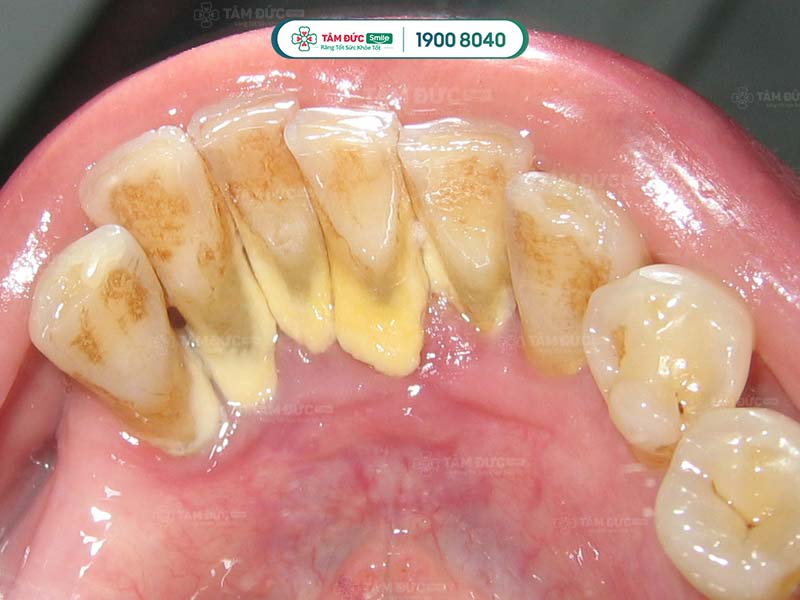

Cao răng được phân chia thành nhiều cấp độ khác nhau, tùy thuộc vào mức độ nghiêm trọng của chúng. Trong đó, cao răng độ 3 là mức độ nghiêm trọng và chỉ đứng sau cấp độ 4. Lúc này, mảng bám đã phát triển dày hơn 2 mm, cứng và bám chặt ở trên răng. Chúng thường có màu vàng sẫm hoặc nâu đậm, Quý khách không thể làm sạch cao răng bằng những phương pháp vệ sinh răng miệng thông thường. Chính điều này đã làm giảm đi tính thẩm mỹ của hàm răng, khiến nhiều người cảm thấy mất tự tin trong quá trình giao tiếp.

Cao răng độ 3 là mảng bám đã phát triển dày hơn 2mm, cứng và bám chặt ở trên răng

Cao răng ở độ 3 thường có màu vàng đậm hoặc nâu, nâu nhạt. Những màu sắc này tương phản với màu răng thật làm tổng thể hàm răng của Quý khách không được đều màu, mất đi tính thẩm mỹ. Một số trường hợp cao răng còn lan ra ở phía ngoài, lộ rõ ở chân răng, bề mặt răng. Đây là lý do khiến nhiều người cảm thấy tự ti trong giao tiếp, công việc.

Cao răng độ 3 có màu vàng đậm, nâu, nâu nhạt gây mất thẩm mỹ